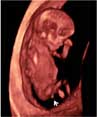

Ecografía 4D de la 12 semanas: Feto con cordón umbilical al hombro

Este bebé, cuya edad gestacional es de sólo 12 semanas, muestra una gran vitalidad de movimientos, a pesar de que el cordón umbilical está peligrosamente situado a la altura del hombro y probablemente alrededor del cuello. El feto parece estar peleándose, como si intentara liberarse de la "atadura" del cordón umbilical.

Ecografía 4D de feto de 12 semanas con cordón umbilical al hombro